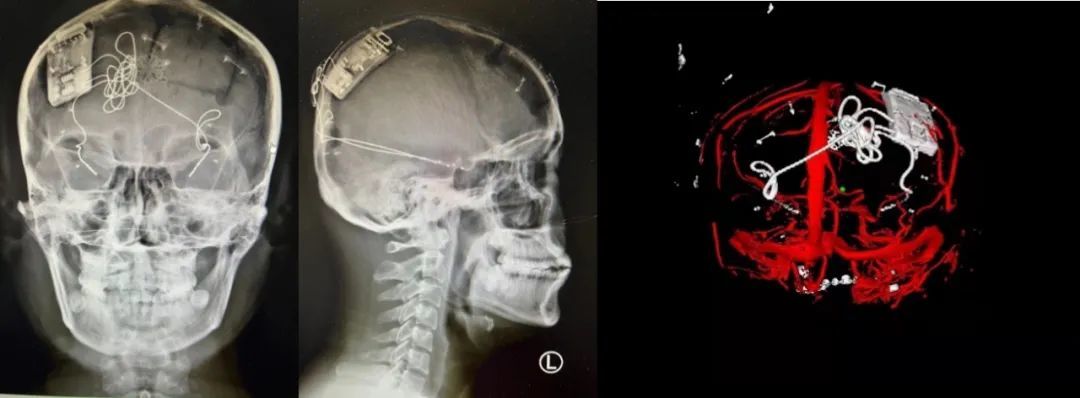

神外前沿訊,2022 年 3 月 9 日,首都醫(yī)科大學(xué)宣武醫(yī)院院長(zhǎng)趙國(guó)光教授,神經(jīng)外科單永治教授帶領(lǐng)的神經(jīng)外科立體定向與功能性腦疾病組團(tuán)隊(duì),成功為一名難治性癲癇患者(雙側(cè)顳葉癲癇)施行了閉環(huán)反應(yīng)性神經(jīng)刺激系統(tǒng) Epilcure?注冊(cè)臨床試驗(yàn)植入手術(shù)(參考閱讀:快訊 | 全國(guó)首款癲癇閉環(huán)刺激系統(tǒng)的注冊(cè)臨床試驗(yàn)啟動(dòng))。

這標(biāo)志著由宣武醫(yī)院作為牽頭單位的 Epilcure?國(guó)家藥品監(jiān)督管理局(NMPA)注冊(cè)臨床試驗(yàn)的首例入組首戰(zhàn)告捷;也標(biāo)志著經(jīng)過(guò)國(guó)內(nèi)臨床與基礎(chǔ)研究團(tuán)隊(duì)艱苦卓絕的努力與攻關(guān),具備自主知識(shí)產(chǎn)權(quán)的“腦機(jī)接口”高新技術(shù)產(chǎn)品,走到了全方位臨床使用前的最后一步。

據(jù)了解,閉環(huán)反應(yīng)性神經(jīng)刺激系統(tǒng)為“腦機(jī)接口”在臨床領(lǐng)域的重要應(yīng)用,該技術(shù)通過(guò)將人工智能芯片植入顱骨,顱內(nèi)電極植入腦內(nèi),晝夜無(wú)間斷監(jiān)測(cè)腦電節(jié)律,一旦預(yù)測(cè)到即將發(fā)生的癲癇,即啟動(dòng)外源性干擾節(jié)律,直接阻斷致癇灶內(nèi)的癲癇形成,精準(zhǔn)的控制環(huán)路的活動(dòng)。

本次手術(shù)過(guò)程順利,術(shù)中刺激器各項(xiàng)指標(biāo)均工作正常,術(shù)后重建顯示電極位置精準(zhǔn),腦電信號(hào)清晰?;颊邽槟行?,入院后診斷為雙側(cè)顳葉癲癇,此類癲癇為開(kāi)顱手術(shù)的相對(duì)禁忌癥,在藥物無(wú)法控制的情況下,傳統(tǒng)治療效果欠佳 。

術(shù)前經(jīng)過(guò)宣武醫(yī)院癲癇多學(xué)科專家團(tuán)隊(duì)詳細(xì)的臨床評(píng)估,包括視頻腦電監(jiān)測(cè)、頭顱磁共振及三維 CT 掃描、腦核醫(yī)學(xué)檢查等,全面評(píng)估了患者病情及致癇灶定位情況。

由于患者臨床診斷為雙側(cè)顳葉癲癇伴海馬硬化,無(wú)法通過(guò)致癇灶切除等傳統(tǒng)外科手術(shù)方式獲益,決定進(jìn)行閉環(huán)反應(yīng)性神經(jīng)刺激系統(tǒng)植入手術(shù)治療。并根據(jù)閉環(huán)神經(jīng)刺激技術(shù)特點(diǎn),為患者“量身定制”植入方案,尤其是電極植入位點(diǎn)和脈沖發(fā)生器固定部位等,為手術(shù)的順利實(shí)施奠定了良好基礎(chǔ)。

團(tuán)隊(duì)根據(jù)術(shù)前計(jì)劃,在手術(shù)機(jī)器人輔助下完成雙海馬長(zhǎng)軸電極及 IPG 植入,術(shù)后重建顯示電極位置精準(zhǔn),腦電信號(hào)清晰。術(shù)后第二天,患者即下床活動(dòng),身體狀況恢復(fù)良好。